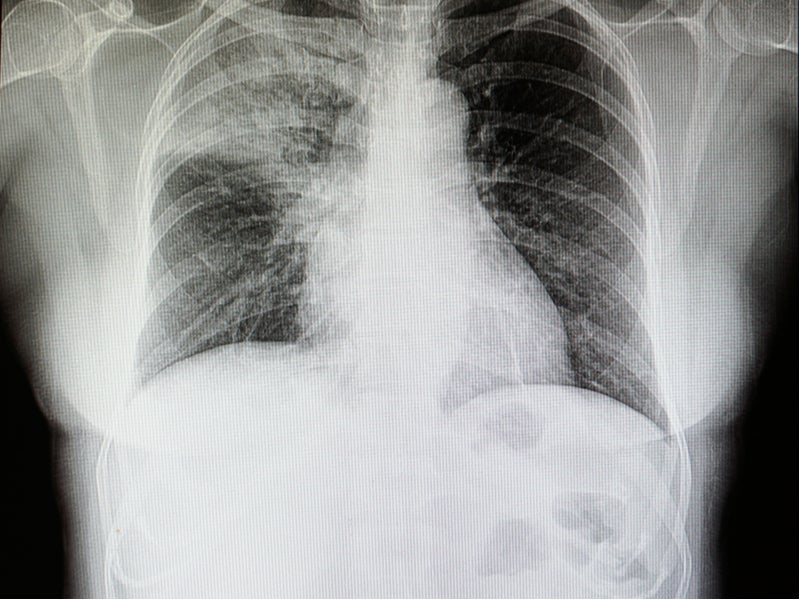

Lung Cancer Screening X Ray

Experience the clarity of Lung Cancer Screening X Ray with our curated collection of comprehensive galleries of images. featuring understated examples of photography, images, and pictures. designed to emphasize clarity and focus. Discover high-resolution Lung Cancer Screening X Ray images optimized for various applications. Suitable for various applications including web design, social media, personal projects, and digital content creation All Lung Cancer Screening X Ray images are available in high resolution with professional-grade quality, optimized for both digital and print applications, and include comprehensive metadata for easy organization and usage. Our Lung Cancer Screening X Ray gallery offers diverse visual resources to bring your ideas to life. Comprehensive tagging systems facilitate quick discovery of relevant Lung Cancer Screening X Ray content. Multiple resolution options ensure optimal performance across different platforms and applications. Time-saving browsing features help users locate ideal Lung Cancer Screening X Ray images quickly. The Lung Cancer Screening X Ray archive serves professionals, educators, and creatives across diverse industries. Instant download capabilities enable immediate access to chosen Lung Cancer Screening X Ray images. Whether for commercial projects or personal use, our Lung Cancer Screening X Ray collection delivers consistent excellence. Professional licensing options accommodate both commercial and educational usage requirements.